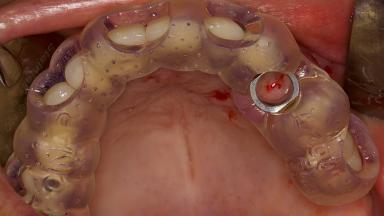

Digitally Guided Sinus Floor Elevation

In this short microlearning module on digitally guided sinus floor elevation, we delve into a specialized aspect of the digital workflow for implant-guided surgery, focusing on the use of digital guides in the sinus floor elevation technique.